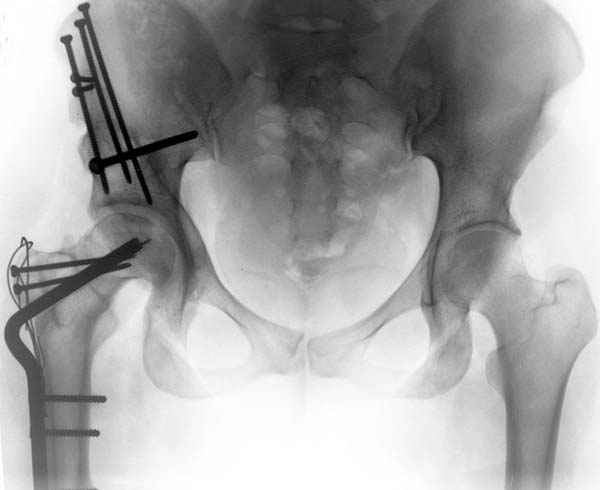

До операции #1

№ 1-3 до операции

Второе, Вы написали о нецелособразности, даже вредности остеотомии в проксимальном отделе бедра и в тазобедренном суставе.

Предлагаю несколько снимков для Вашего внимания и вашего "с 1946 года сложившегося активного достаточно прогрессивного коллектива”, а с доктором К.Креттеком при нашей встрече (не менее двух раз в год) на наших совместных конференциях найду возможность обьясниться с ним насчет остеотомии.

№ 4-6 после операции при дисплазии тазобедренного

сустава